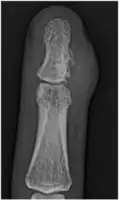

A well-defined area of bone loss in the medulla of the bone is seen on x-ray.[2]

X-Ray right middle finger: juxta-cortical chondroma -